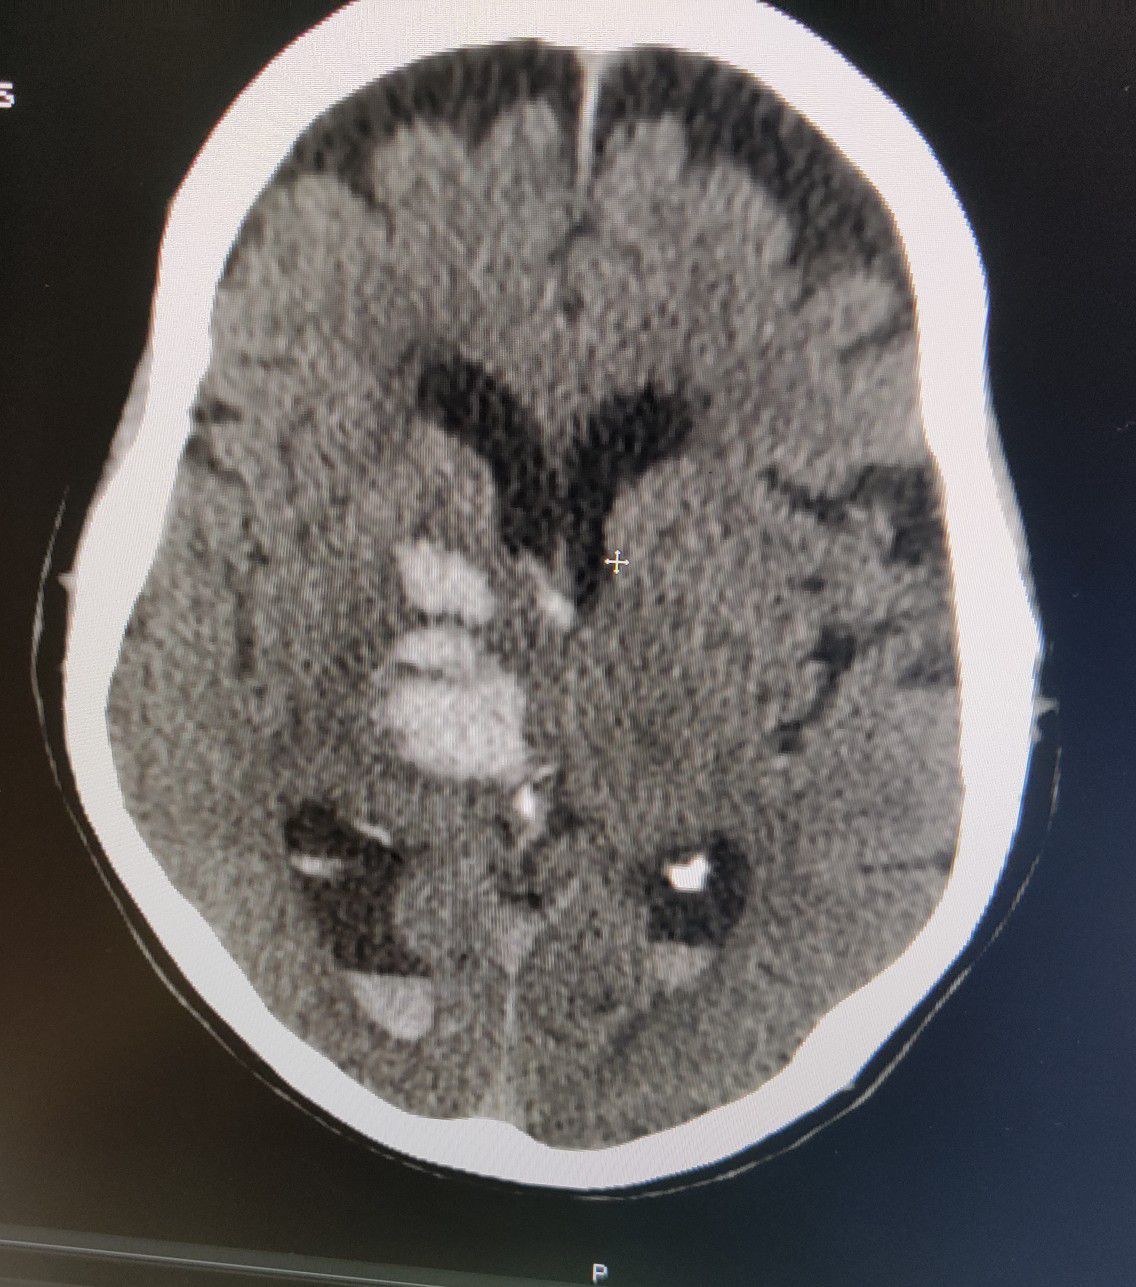

Hemorrhagic CVA

Brain

Cva

Hemorrhagic